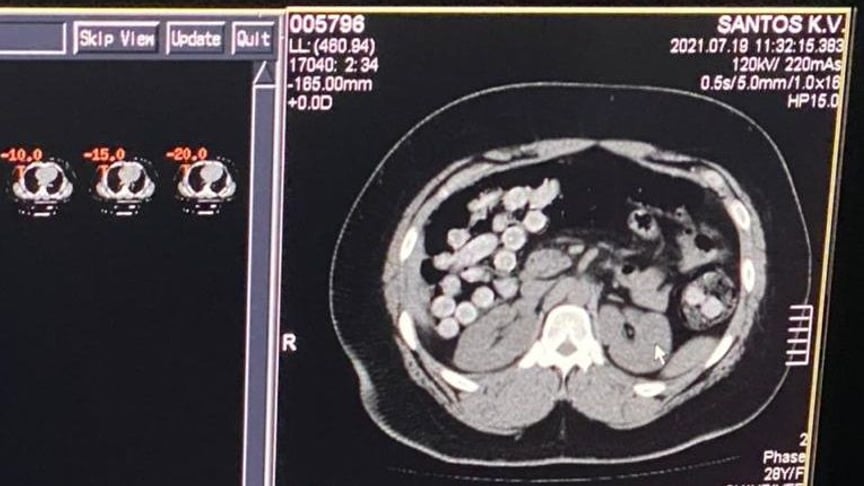

Загалом виявили кокаїну на 2 кг. Один зі зловмисників переміщував наркотики в особистих речах. Інший намагався перевезти через державний кордон понад 1 кг кокаїну у кишково-шлунковому тракті.